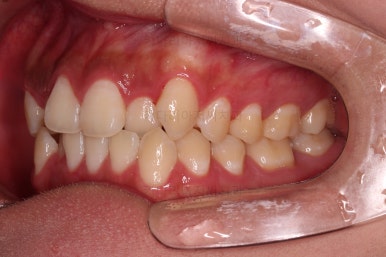

부산치아교정치과 초진 시 입안의 모습입니다.

앞니쪽이 위아래 모두 삐뚠 상태였고요.

왼쪽은 덧니로 툭 튀어나가 있고, 상대적으로 작은 앞니는 안으로 말려 들어가 아랫니와도 거꾸로 물리는 상태였습니다.

어금니도 물론 약간 삐뚤긴 하지만 앞니만큼 심한 상태는 아니었고 맞물리는 기능도 큰 불편함은 없으신 상태였습니다.